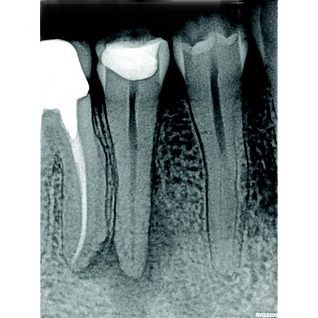

Radiografía digital (RVG): imágenes inmediatas con mínima radiación y máxima definición.